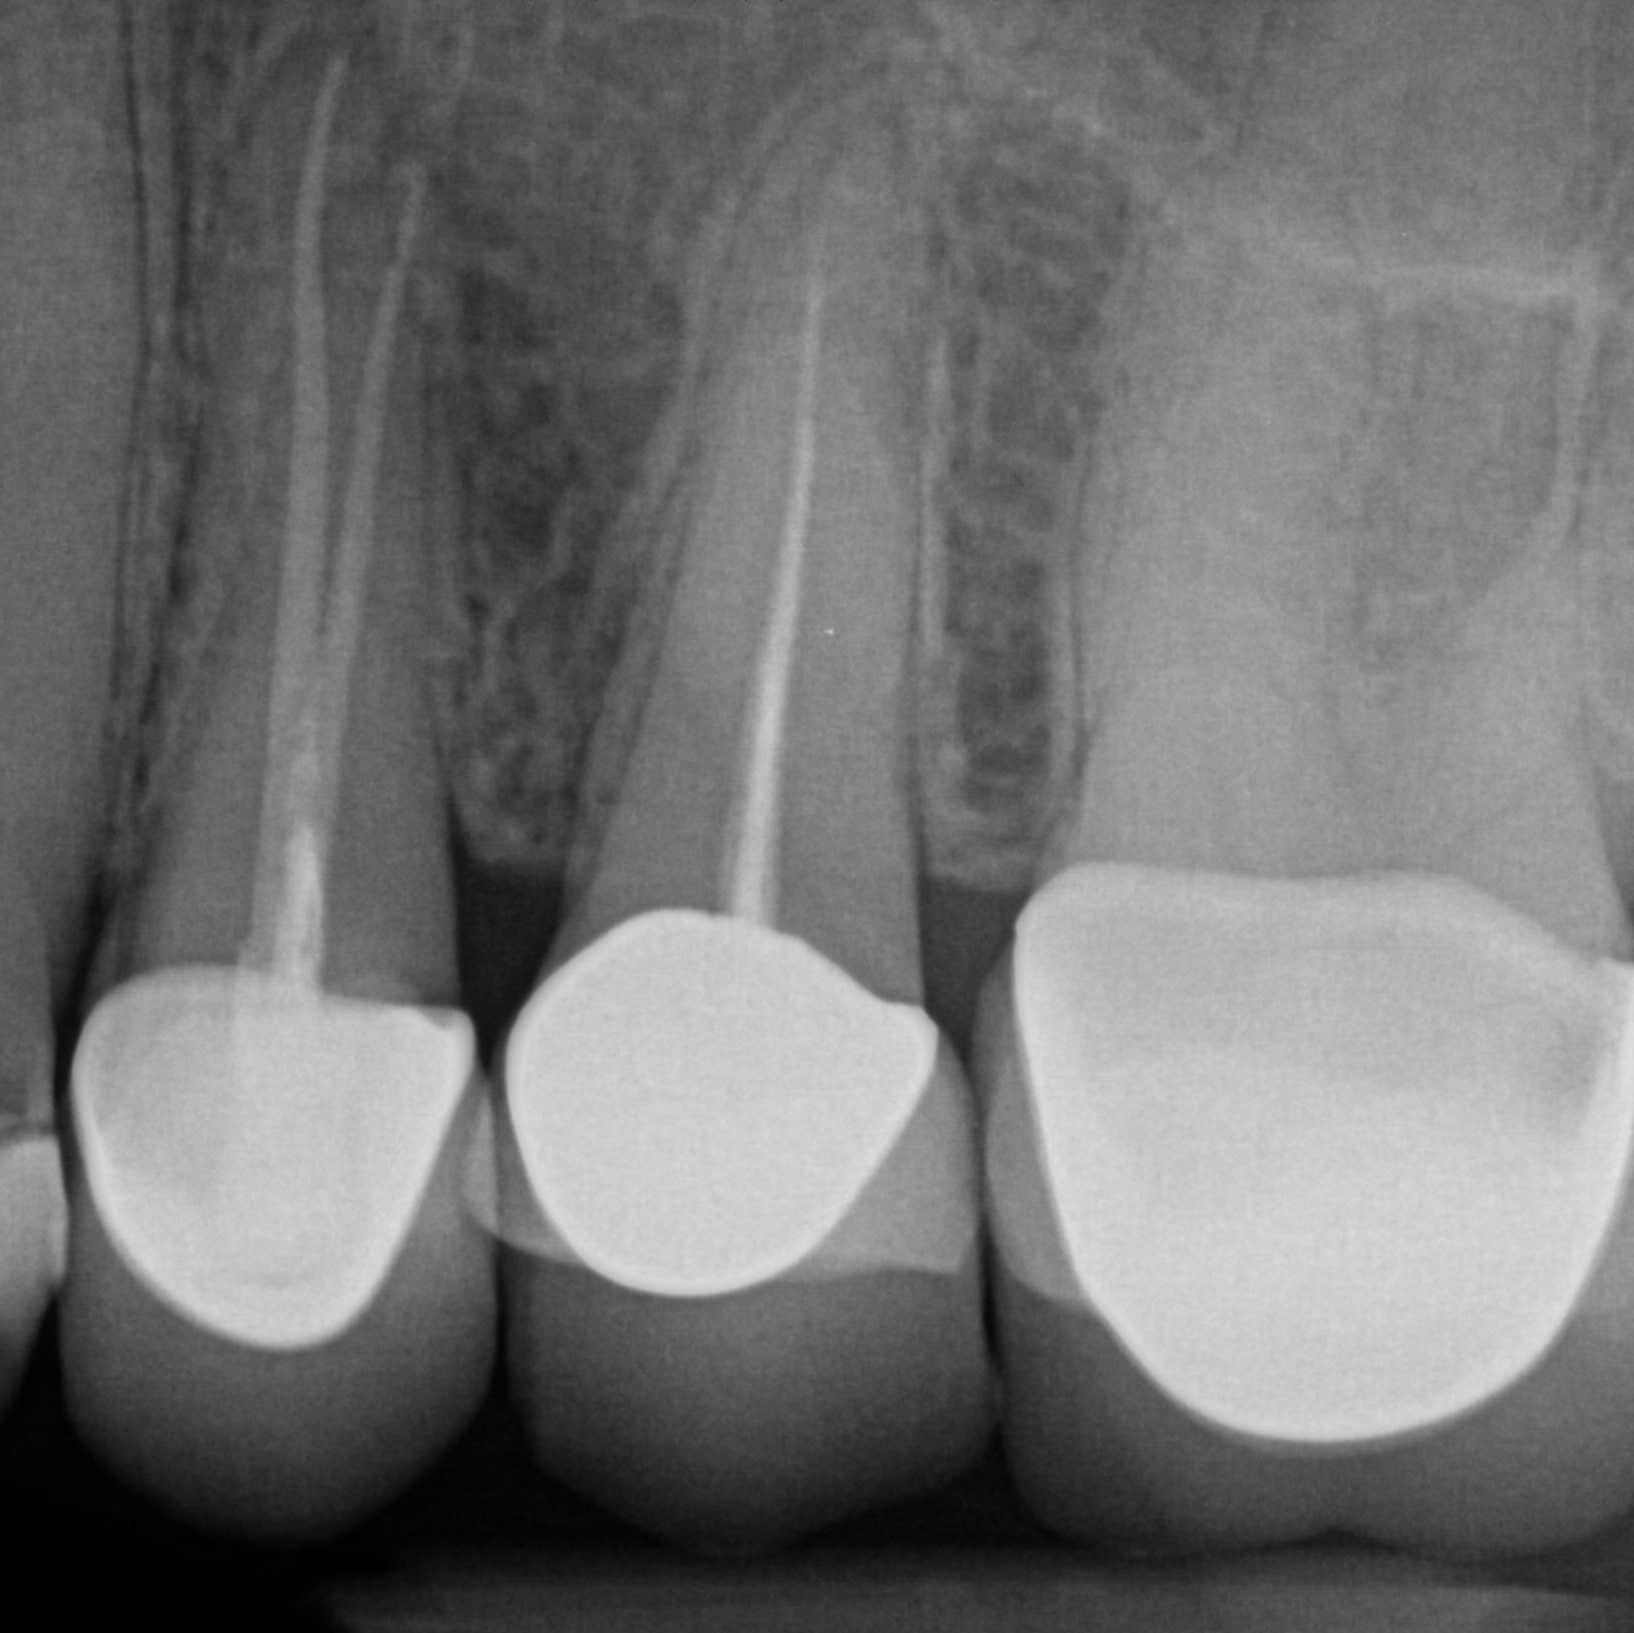

Digital 2-D X-ray

Two-dimensional digital x-ray is still the best technology for decay diagnosis. Digital 2-D x-rays offer higher resolution at a fraction of the radiation of film and the images are instantly available.